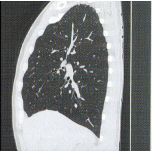

サジタル断面 -